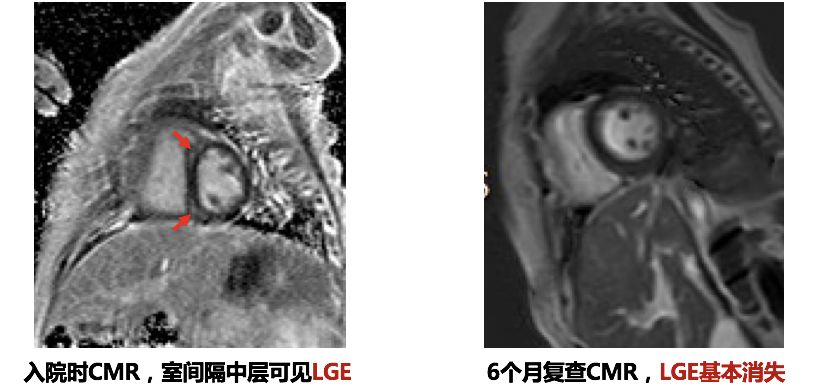

➤ 本病例3例患儿在初始评估后均行CMR检查

CMR:左心室增大,左心室舒张末期内径59.4mm,EF 13.3%

电影MRI:左心室室壁运动减低,收缩功能下降。心包内见少量液性信号影。

心肌延迟强化成像:中央段-心尖段下壁及前壁可见心肌中层线样高信号影

6个月复查CMR

入院时CMR可见右室明显增厚,经积极治疗,6个月复查右室心肌厚度基本恢复正常

复查CMR

• 儿童HF病因多由感染诱发,新生儿期常见的病因为先天性心脏病,婴幼儿及儿童期HF多为感染诱发的心肌炎、心肌病等

• CMR检查能够清晰显示心肌的情况并帮助医生判断预后,建议生命体征稳定的HF患儿行CMR检查,并定期随诊